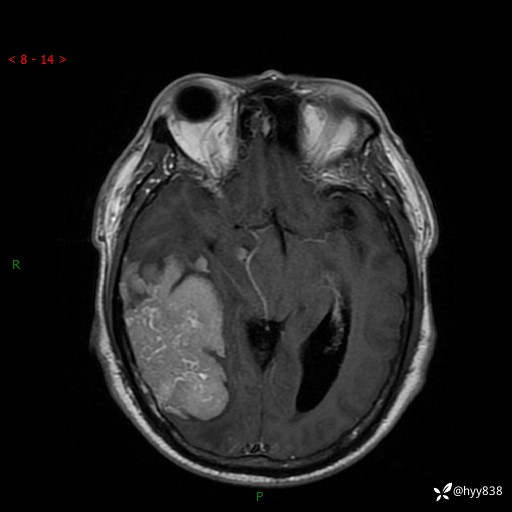

患者性别:男

患者年龄:56岁

简要病史:外院CT提示脑膜瘤,为进一步诊治来我院

临床诊断:颅脑占位

颅脑MRI平扫+增强